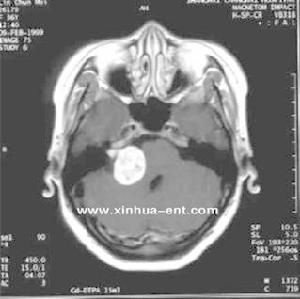

4.放射學檢查(1)顱骨X線片:岩骨平片見內耳道擴大、骨侵蝕或骨質吸收。(2)CT及MRI掃描:CT表現為瘤體呈等密度或低密度,少數呈高密度影像。腫瘤多為圓形或不規則形,位於內聽道口區,增強效應明顯。MRIT1加權像上呈略低或等信號,在T2加權像上呈高信號。第四腦室受壓變形,腦幹及小腦亦變形移位。注射造影劑後瘤實質部分明顯均一強化,囊變區不強化。

(3)CT及MRI檢查:目前聽神經鞘瘤診斷的標準是Gd-DTDA增強的MRI,特別是當腫瘤很小(<1cm)或在內聽道內,CT掃描陰性又高度懷疑腫瘤存在時應該進行GD-DTPA增強的MRI。CT與MRI兩種檢查有相輔相成的作用,如CT發現有病側內聽道擴大時,增強CT可發現腫瘤對於估計中顱窩入路時顳骨的氣化程度及高頸靜脈球與後半規管及底的距離有幫助。如果病人已作了CT而腫瘤較大,MRI可提供對腦幹壓迫的範圍Ⅳ腦室是否通暢腦積水、是否存在的情況對可疑聽神經鞘瘤或CT檢查難於確定時,全序列的MRI可做出鑑別診斷。但也要注意Gd-DTPA的可能假陽性,這與內聽道內神經的炎症或蛛網膜炎有關;任何小的接近底部的增強病變應該在六月後作MRI複查,以評估其生長情況。